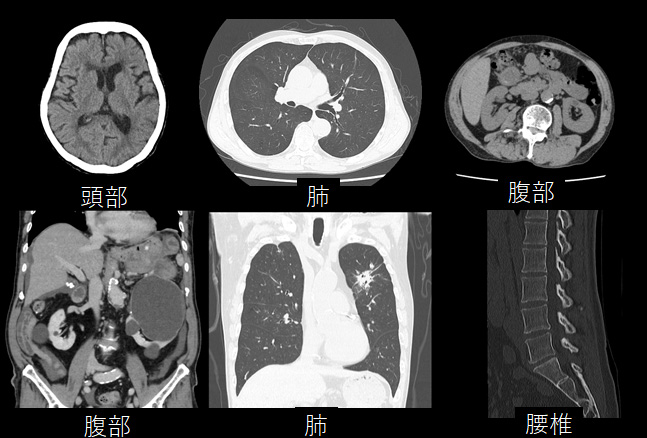

中外医学社 | 書籍詳細。臨床心臓CT学-基礎と実践マネージメント | 小山 靖史, 鈴木 諭。アプリケーション(心臓領域) | REVORAS。【N☆】令和6年(新米)コシヒカリ1等米10キロ。CT検査 | 戸畑共立病院。オプション検査 | 人間ドック健診センター | 大田区蒲田 牧田。。桜橋渡辺未来医療病院 MDCT検査予約。医学出版_循環器ナーシング16年6月号。CT検査 | 戸畑共立病院。心臓特化型画像診断センター「心臓画像クリニック(CVIC)飯田橋。朝倉書店『内科学』(第12版)デジタル付録。メジカルビュー社|診療放射線技師|心臓CT活用マニュアル。心臓Ⅰ:Step and shoot technique 岩城 卓(横浜栄共済病院。「臨床心臓CT学 基礎と実践マネージメント」小山 靖史定価: 22000円 (20000円+税)ぼぼ未使用でパラパラと見ただけで、状態はよいと思われます。書き込みも見返しましたがありませんでした(万が一あったら申し訳ございません)。表面に多少のスレやキズはあります。また天面に名前の印鑑がありマジックで消しています。あくまで写真のものをお渡しということでよろしくお願い致します。ご質問や価格交渉ありましたらメッセージくださいm(._.)m循環器内科、内科、カテ、カテーテル、CAG、PCI、FFRインターベンション、読影、放射線冠動脈、動脈硬化冠動脈疾患、虚血性心疾患、狭心症、心筋梗塞高血圧、糖尿病、脂質異常症、肥満